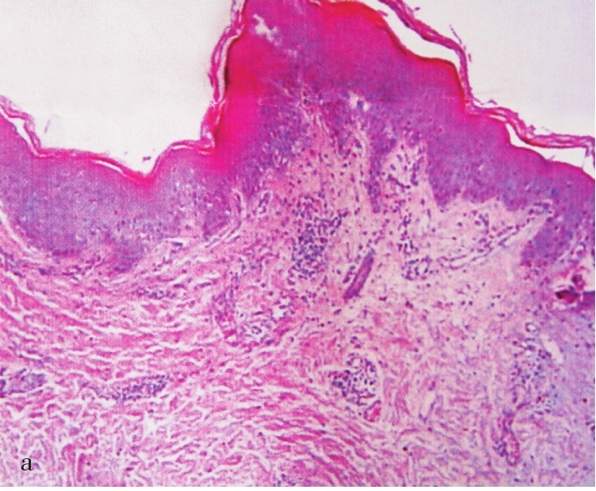

专科情况:腹部散在大小不等、形状不规则红斑,部分呈环形,躯干广泛白色薄鳞屑,右上肢片状红斑,伴针尖大小脓疱,散在红丘疹,如图

组织病理: